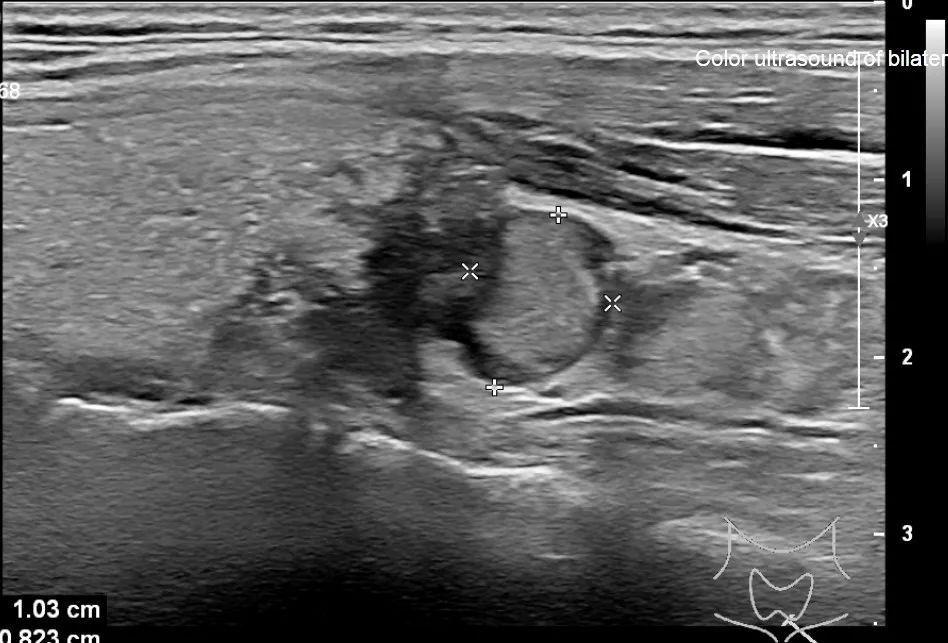

在医院里,小美这类病例并不罕见。她按照医嘱接受了超声波检查,检查结果显示,她的甲状腺左侧叶存在一个直径约2.5厘米的结节,同时在左侧颈部发现了一个直径为1厘米的淋巴结。据统计,全球约有30%至50%的人在其一生中可能检测出甲状腺结节,其中,40岁以上的女性发病率高于男性。《中国癌症报告》指出,在过去20年里,女性甲状腺癌的发病率增速显著超过男性。

需注意的是,超声检查中,若甲状腺结节形态不规则、边缘模糊,其恶性可能性约为10%。特别是对于有甲状腺癌家族史或颈部曾受辐射的人群,恶性结节出现的几率会明显上升。对于被超声诊断为1/2/3类、直径不足1厘米且无症状的结节,一般建议进行观察及定期复查。